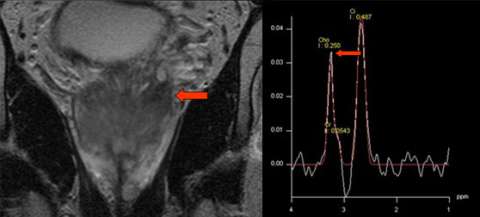

LEFT: Coronal T2-weighted image: abnormal signal extends to seminal vesicles (arrow)

RIGHT: Sample spectrum from spectroscopic imaging: elevated choline (Cho) relative to citrate (Ci)